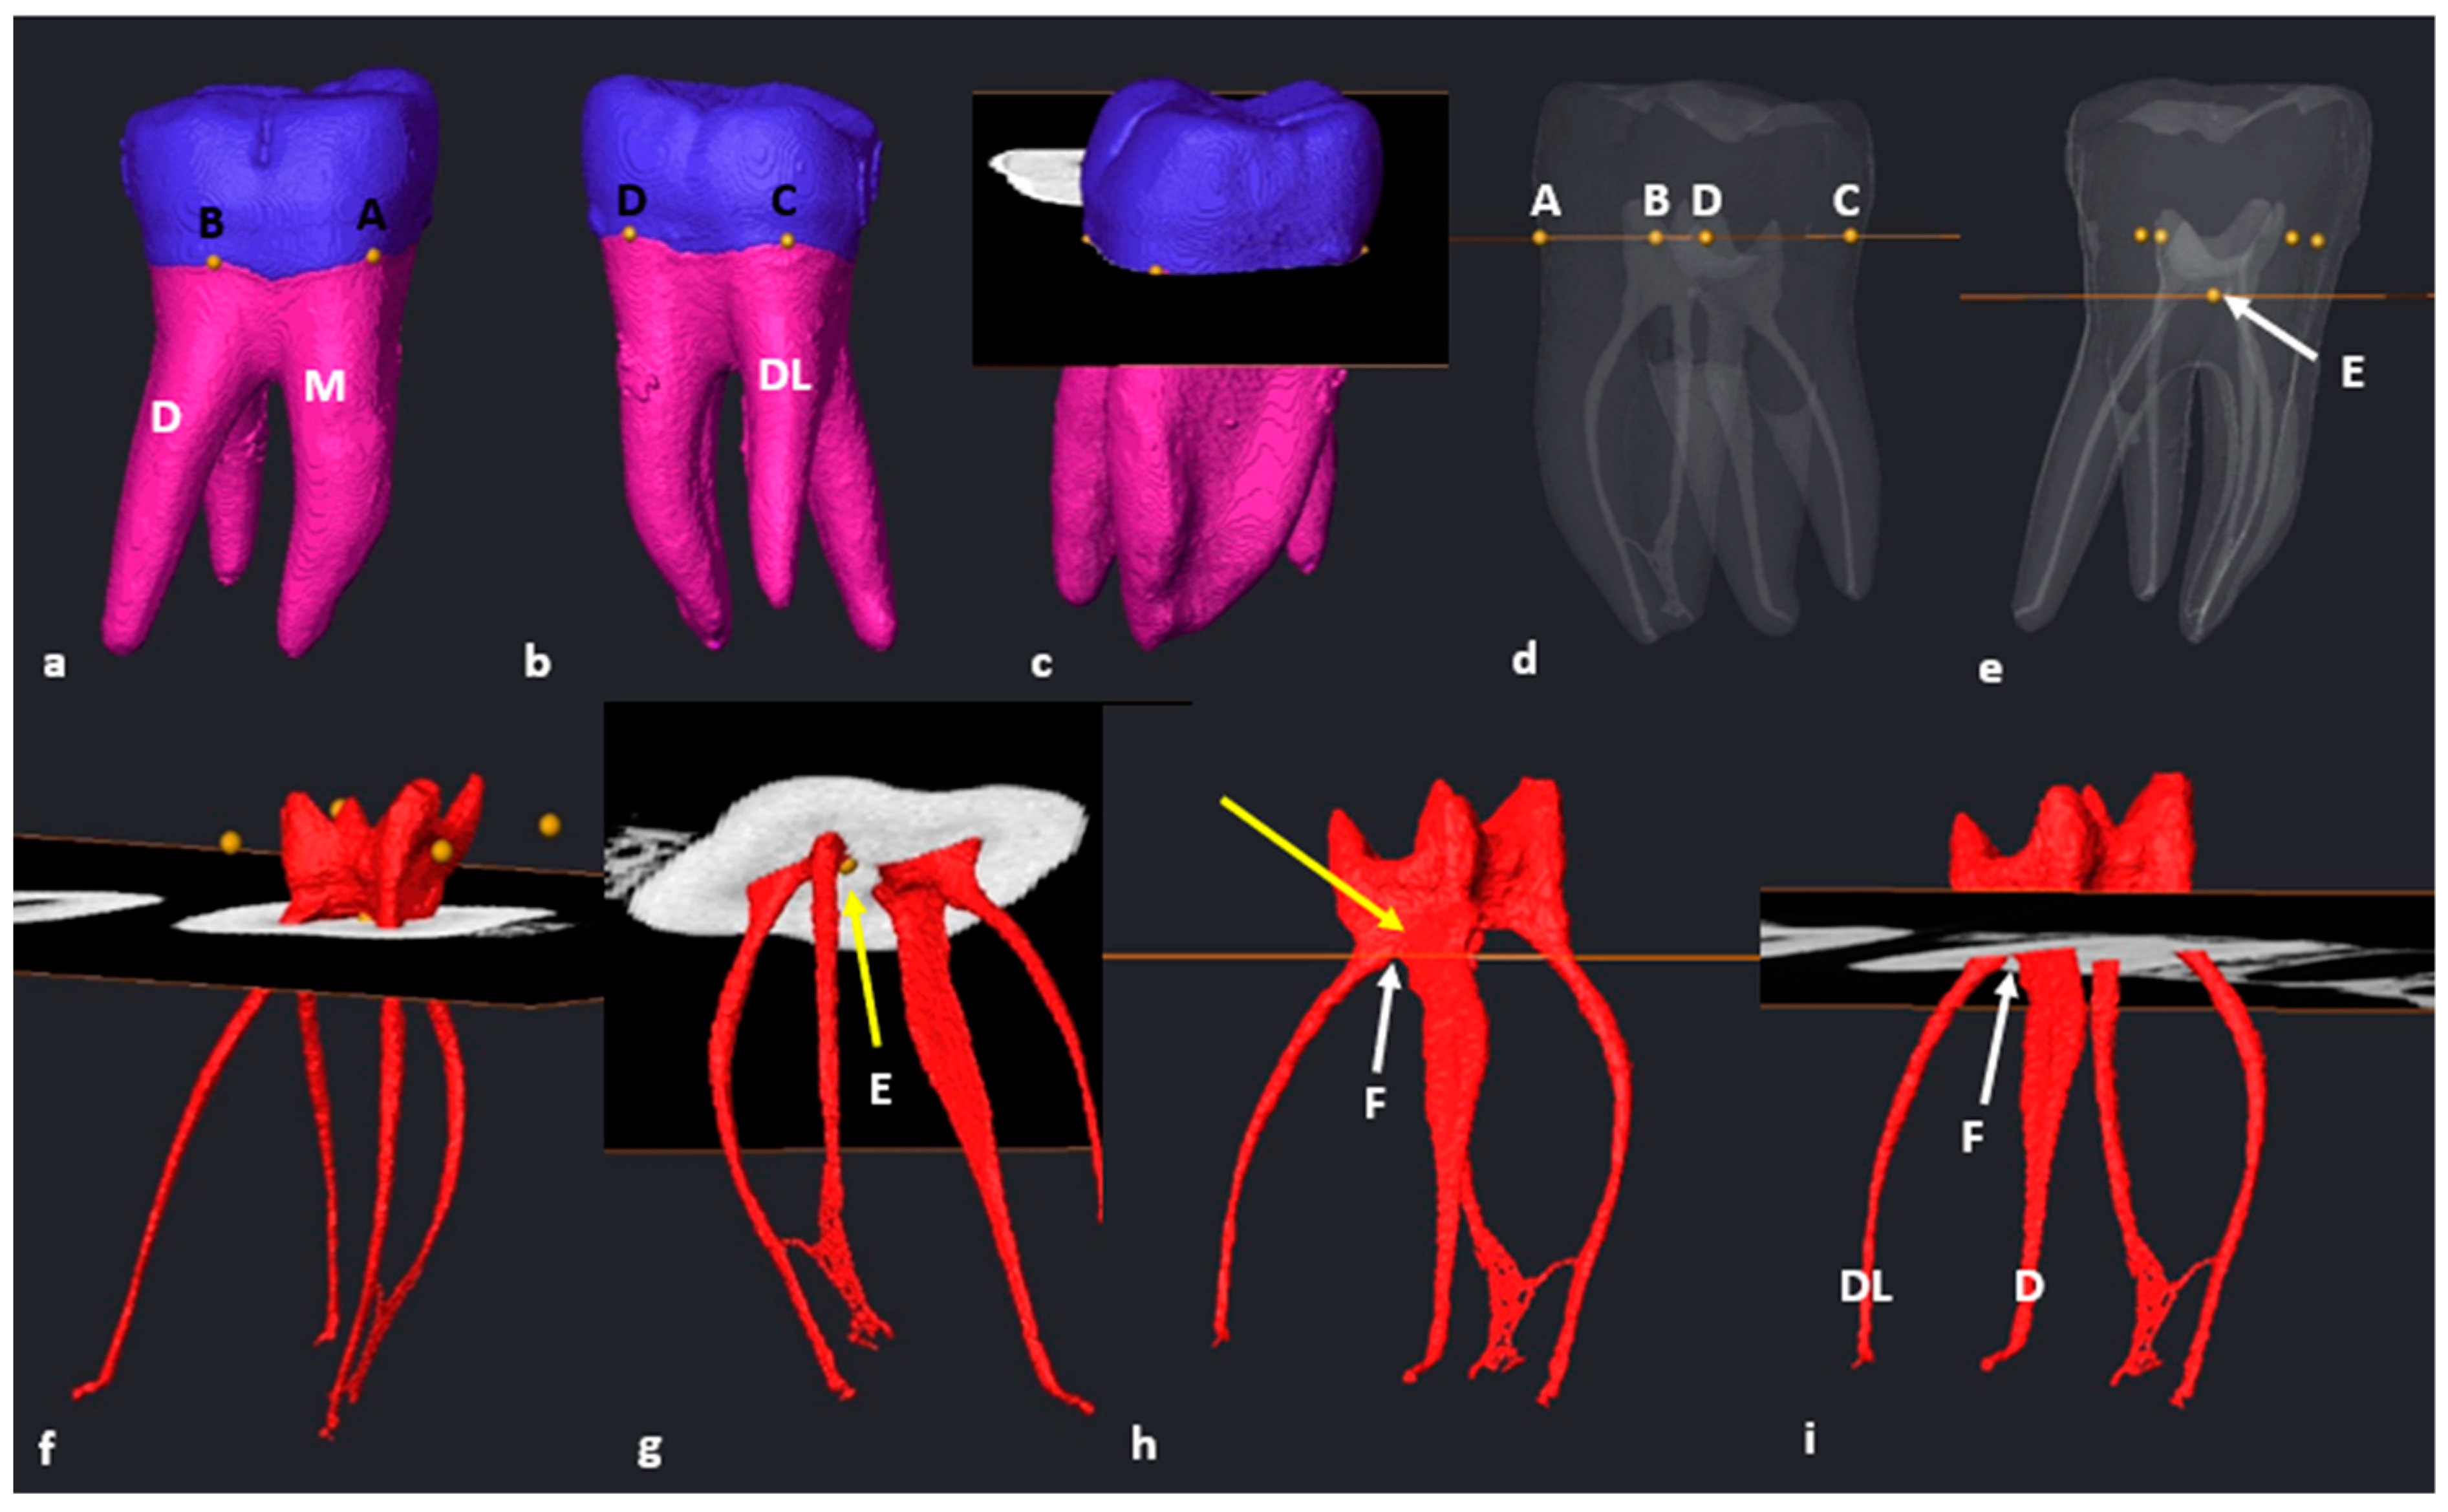

2.6. Segmentation and Landmark Identification

3.3. Maxillary First Molars: Three Separate Roots

3.4. Maxillary Molars: Variants in Mesial or Distal Bifurcations